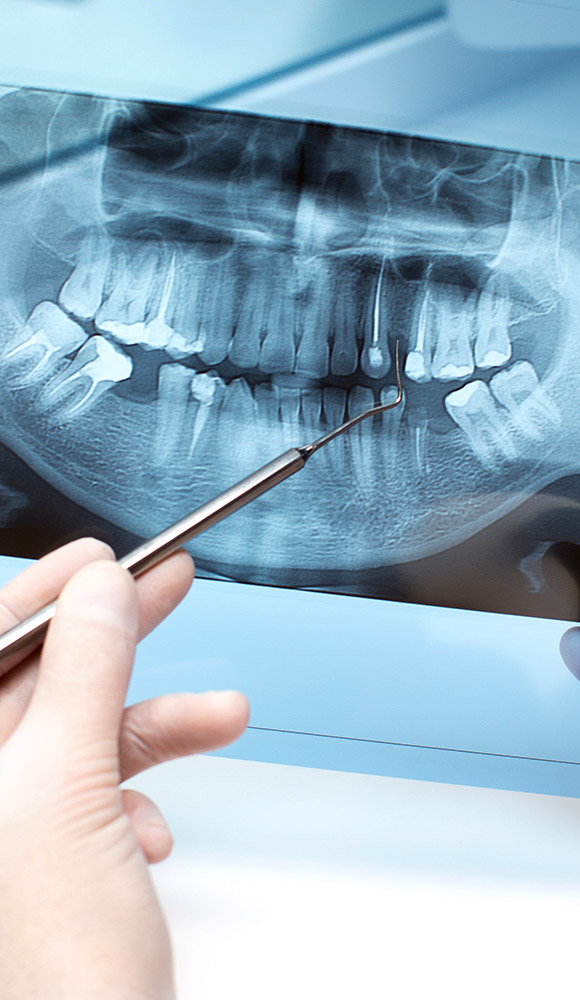

Ortopan

Ortopan je panoramski rendgenski snimak kojim se prikazuju obe vilice zajedno sa zubima, korenovima i okolnim koštanim tkivom. Idealan je za prvi pregled kod stomatologa, jer daje potpun i brz uvid u stanje celokupne usne šupljine. Pomaže u otkrivanju skrivenih problema kao što su neiznikli zubi, ciste ili patološke promene u viličnoj kosti.